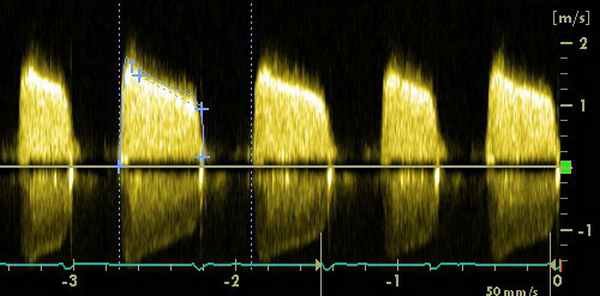

- ЭхоКГ. ЭХОКГ позволяет определить: структуру клапана (двустворчатый клапан, утолщение створок, фиброз, кальциноз, вегетации), характер его движения (подвижность створок, степень открытия) и площадь отверстия; изменения корня аорты (постстенотическая дилатация), объем левого желудочка, выраженность гипертрофии левого желудочка, нарушения локальной сократимости левого желудочка (указывающие на ИБС), ФВ, объем левого предсердия, состояние других клапанов. Доплеровское исследование позволяет с высокой точностью определить градиент давления между аортой и левым желудочком.

Средний систолический градиент между аортой и ЛЖ на уровне аортального клапана менее 50 мм рт. ст. – гемодинамически малозначимый аортальный стеноз, 50 – 80 мм рт.ст. – умеренный аортальный стеноз, более 80 мм рт.ст. – резкий аортальный стеноз.

• Площадь отверстия • Пиковая скорость >4.0 м/с.

• Средний градиент давления >40 мм рт. ст.